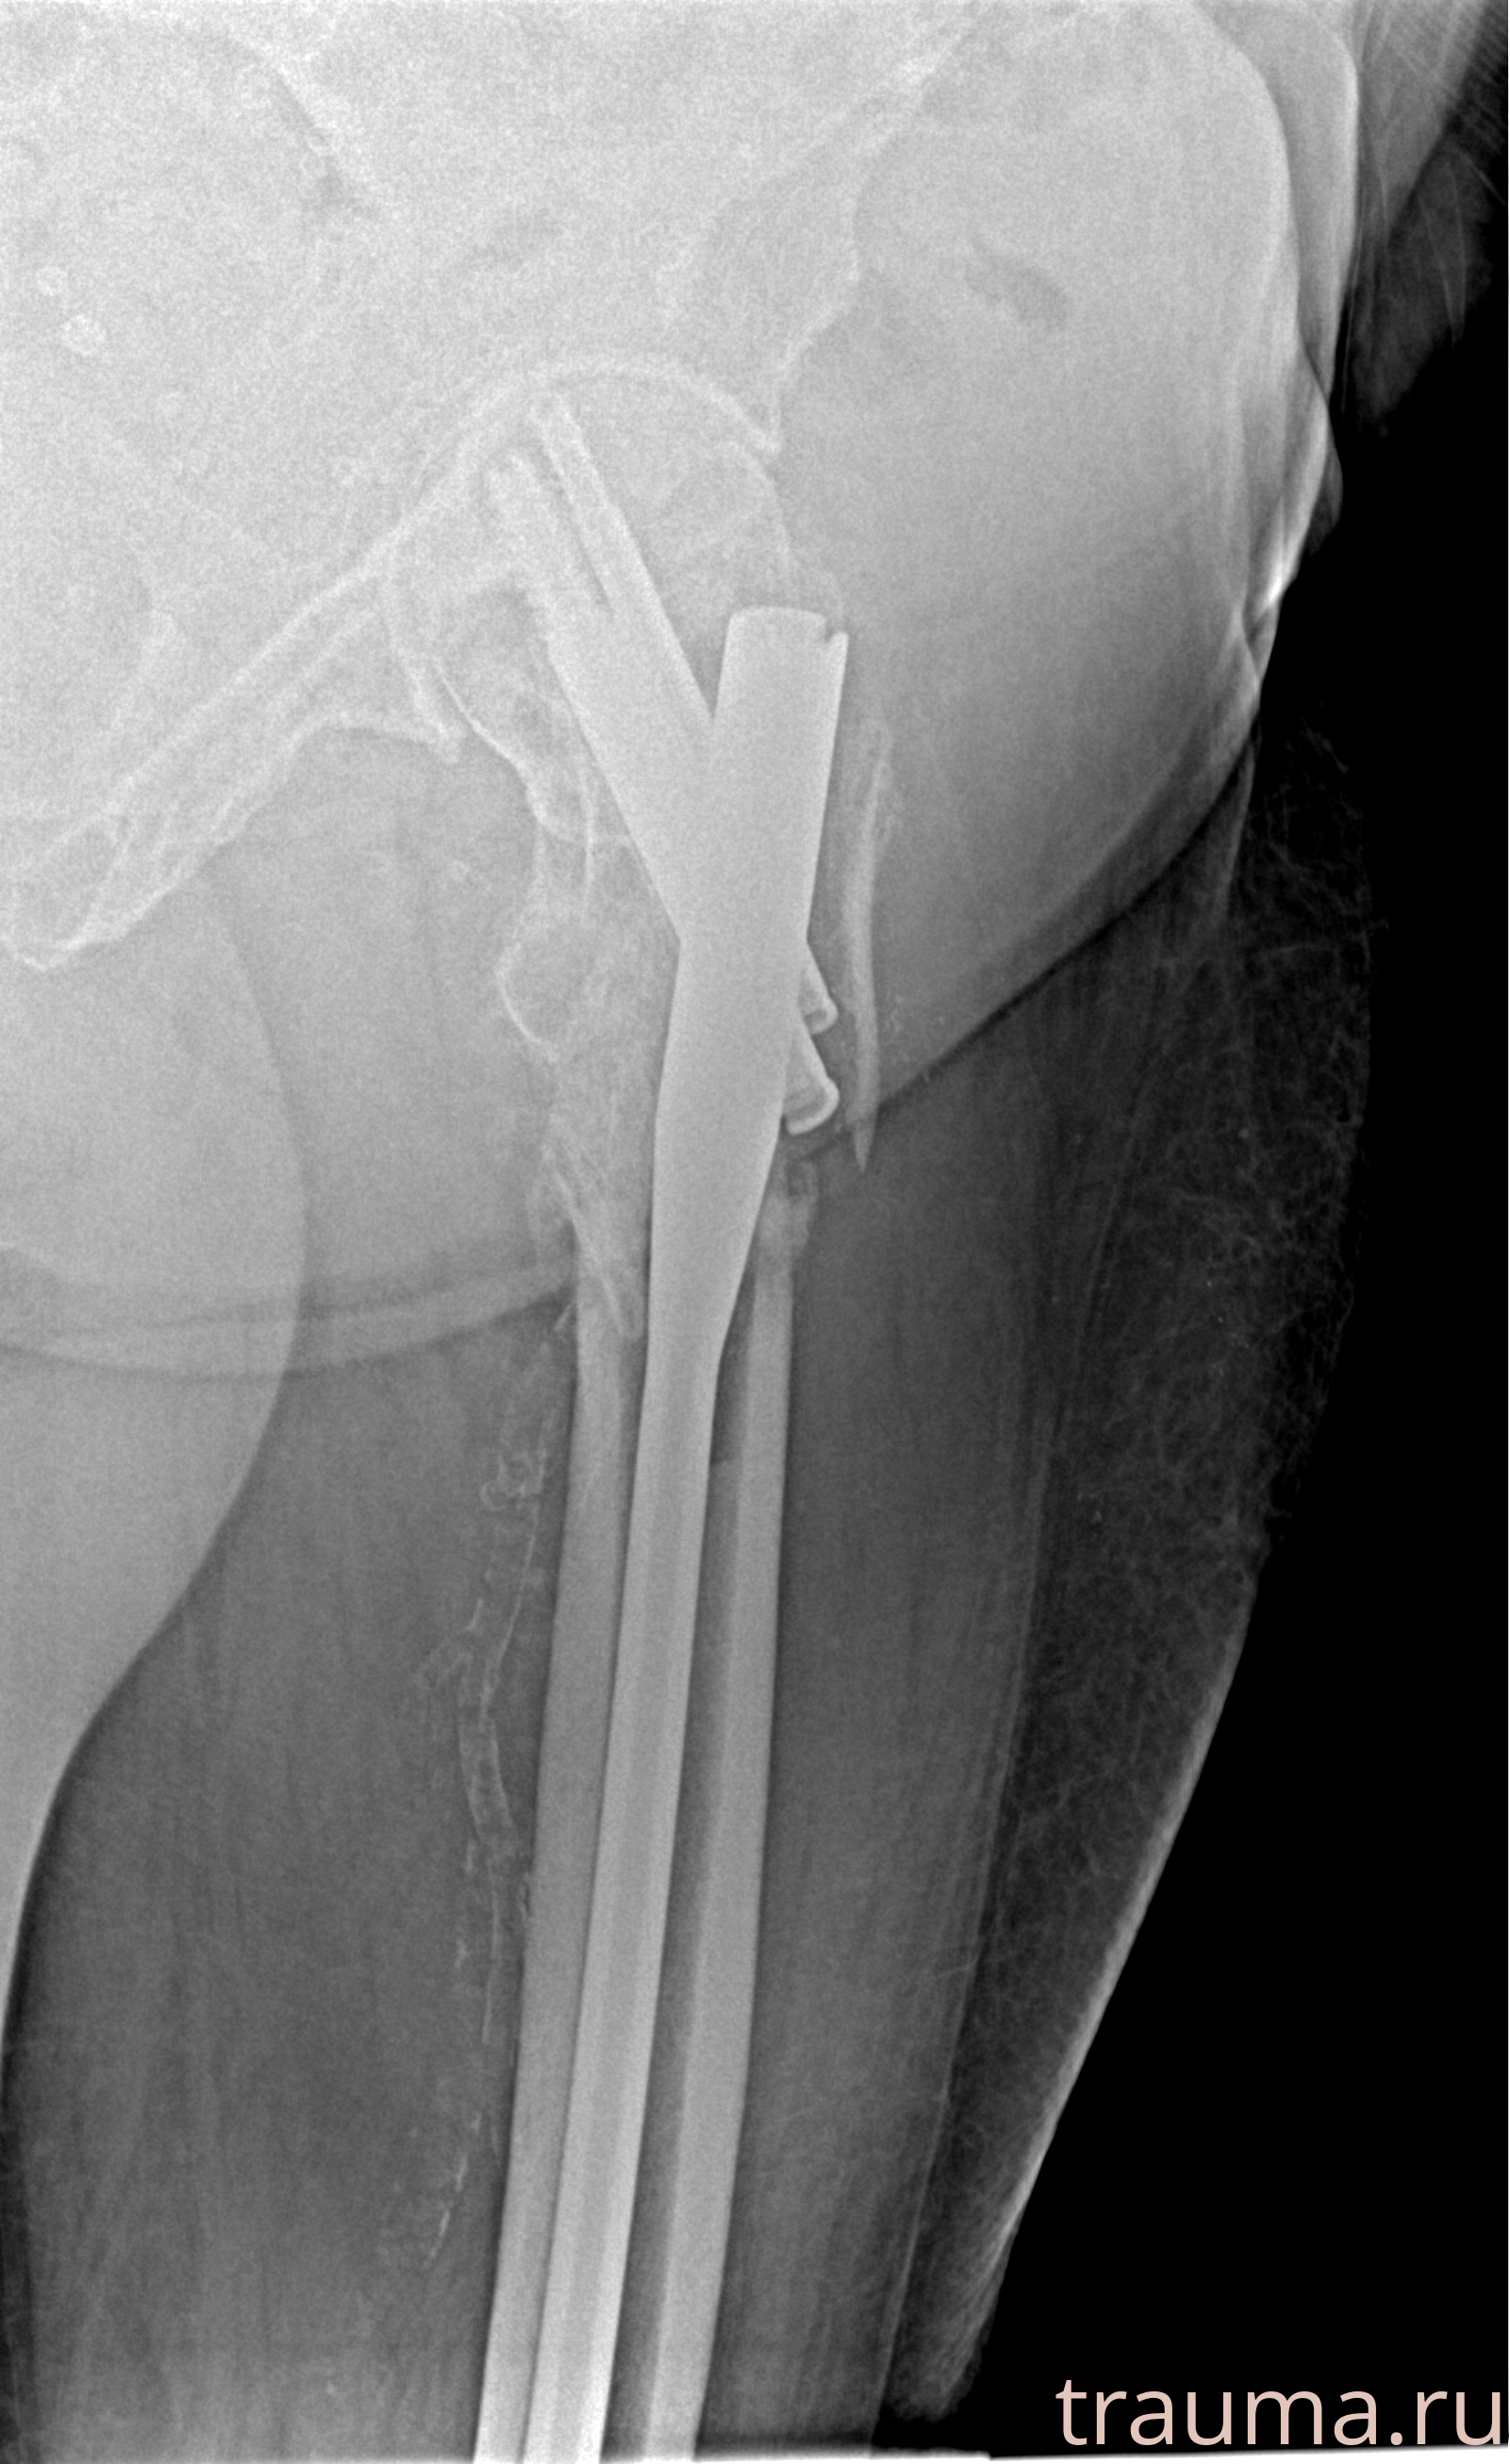

Рентгенограммы

Рентген на дому: по вашему адресу приезжает врач-рентгенолог, травматолог-ортопед с мобильным рентгеновским аппаратом, проводит диагностику травмы или заболевания, делает необходимые рентгенограммы, дает рекомендации по дальнейшему лечению. Получить качественные снимки в домашних условиях возможно благодаря уникальной методике, разработанной МосРентген Центром для института  Склифосовского